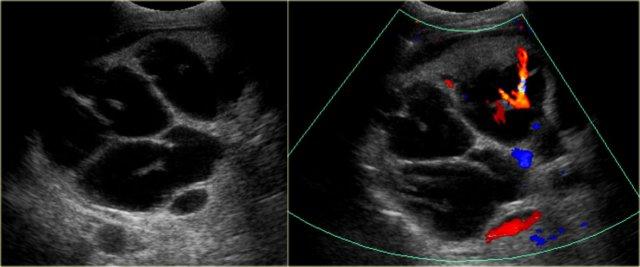

Bên trái là hình ảnh của một bệnh nhân mắc bệnh Caroli.

Lưu ý tình trạng giãn ống mật trong gan và đường kính bình thường của ống mật chủ (ống mật ngoài gan).

Đặc điểm điển hình của bệnh Caroli là giãn ống mật trong gan.

Tình trạng giãn có thể rất lớn và dạng túi như trong trường hợp bên trái, hoặc có thể có dạng tuyến tính.

Một dấu hiệu rất quan trọng là dấu hiệu chấm trung tâm.

Chấm trung tâm tương ứng với tĩnh mạch cửa được bao quanh bởi các ống mật giãn.

Bên trái chúng ta thấy một chấm nằm bên trong các ống giãn.

Khi bật Doppler màu, chúng ta sẽ nhận thấy các cấu trúc này có dòng chảy máu và đại diện cho các tĩnh mạch cửa.